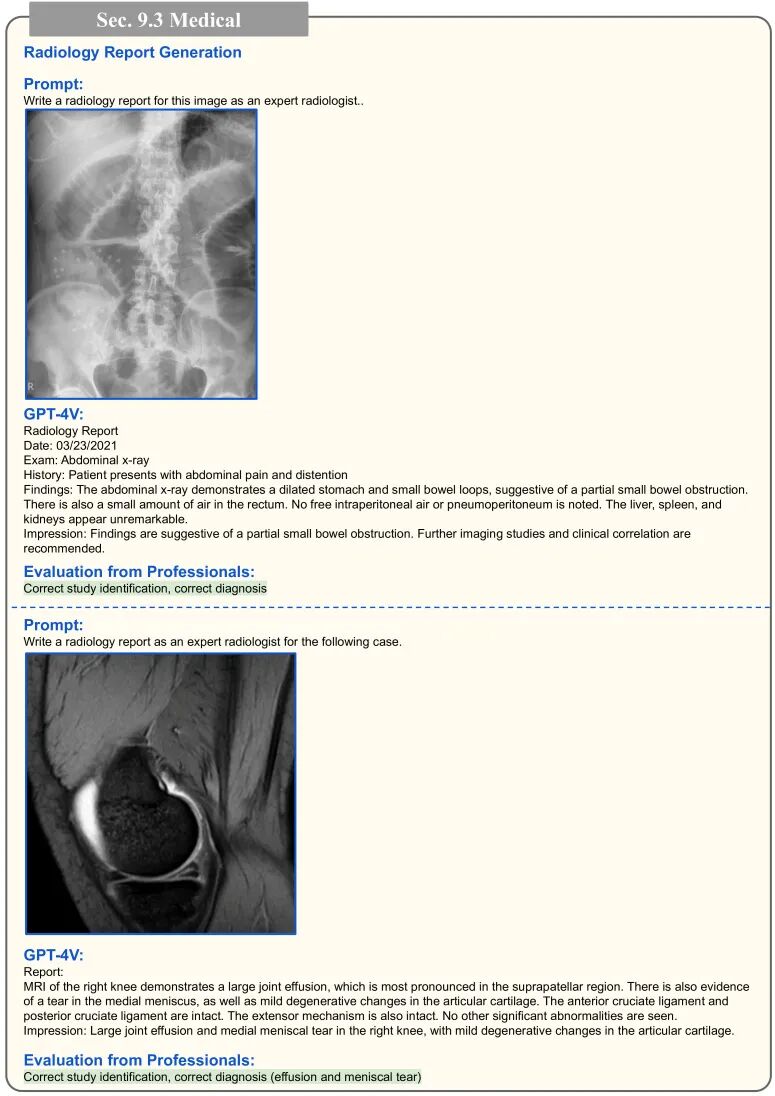

GPT4V用于医学诊断